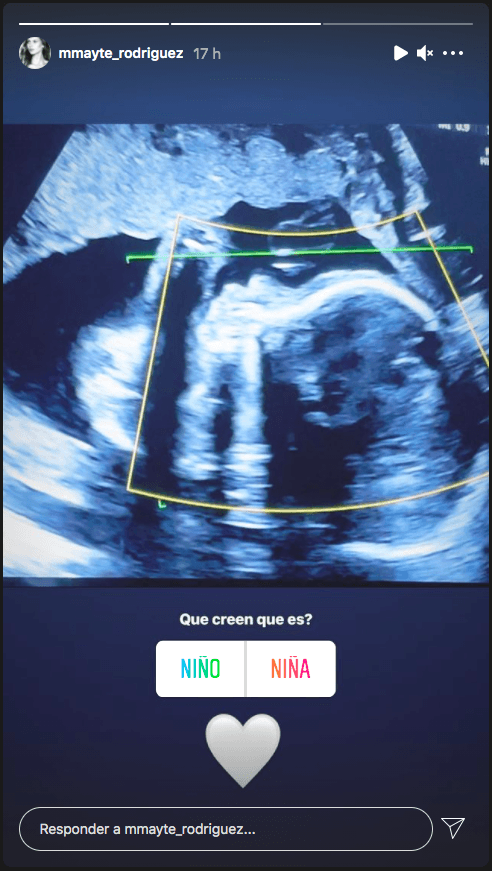

En tanto que una tercera historia vino con sorpresa: Rodríguez compartió una captura de su ecografía, lo que evidentemente califica como la primera imagen pública de su bebé.

Allí también abrió la interrogante: “Qué creen que es?”, dejando los botones de encuesta de Instagram. 19 horas después de su publicación, la opción niña acaparaba las preferencias con un 65%.